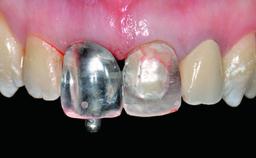

A 32-year-old female Caucasian patient with a compromised maxillary right central incisor was referred to us by a general dentist. Her chief complaints were discomfort and mobility of tooth 11 with unsatisfactory esthetics due to discoloration. The patient reported a previous trauma, some years earlier, as the origin of pathology on the afflicted tooth. Anamnesis was negative for any other dental or periodontal pathology in the remaining dentition. The patient did not take any medication and reported to be a light smoker (5–10 cigs/day). She had high esthetic expectations of her treatment. The extraoral examination revealed a high smile line with full exposure of her maxillary teeth and surrounding soft tissue in the area between the second premolars.

Loading Protocol Conventional or early

Retention Screw-retained Screw-retained

Provisional Implant-Supported Prosthesis Prosthodontic margin > 3 mm apical to mucosal margin Prosthodontic margin > 3 mm apical to mucosal margin

Interim Prosthesis during Healing Fixed Fixed